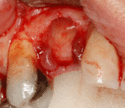

يتم اجراء جراحة الأسنان في العيادة تحت ظروف معقمة، من قبل طبيب أسنان متخصص في زراعة الأسنان و/أو جراحة الفم والفك. يتم تخدير المريض بواسطة حقنة بمخدر موضعي في منطقة دواعم السن، كما هو الحال في علاجات الأسنان العادية (في بعض الأحيان هناك حاجة بتوسيع نطاق التخدير، وفقاً لموقع الغرسات).

اذا كان العظم على استعداد لتلقي الزرع (أحيانا بعد سلسلة علاجات مسبقة)، يمكن البدء بعملية زرع الاسنان. يتم تثبيت المسامير المعدنية اللولبيه براغي، بعظم الفك. في سلسلة اخرى من العلاجات بعد فترة من ادخال البراغي، تبدا عمليات اعادة البناء عن طريق أخذ القياسات وانشاء التاج/الجسر. عندما يدور الحديث عن فترة الانتظار بين تركيب الغرسات وبين تنفيذ الاستبناء النهائي، فان هنالك اكثر من نهج واحد. النهج المتبع غالبا هو الانتظار لمدة 6 أسابيع على الأقل حتى تلتئم الانسجة، وأحيانا تصل فترة الانتظار لعدة شهور.

- النزيف - خاصة في منطقة العملية نتيجة لتعرض الانسجة للرضح. يمكن ان يحدث النزيف فورا بعد الجراحة، وقد يحدث بعد 24 ساعة من الجراحة وفي حالات نادرة بعد اسابيع او اشهر. يحدث النزيف نتيجة تمزق ونزف احد الاوعية الدموية في دواعم السن. اذا كان النزيف شديدا، الامر الذي يعتبر نادرا، يجب القيام بنزحه.

يحدث النزيف عندما تنفتح الاوعية الدموية الصغيرة في اللثة وتنزف. في الحالات التي يشتد فيها النزيف هناك حاجة بالتصريف لكن هذا نادر جدا. مخاطر التخدير – عادة تكون الاعراض مرتبطة بفرط التحسس تجاه ادوية التخدير (استجابة ارجية). في بعض الحالات النادرة، قد يظهر رد فعل خطير يتمثل بهبوط شديد في ضغط الدم (صدمة تاقية - Anaphylactic shock).[1]